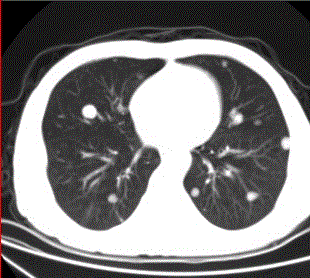

问题 患者男,45岁,因肝硬化、肝癌行肝移植术后6个月,咳嗽2周,来院复查。CR及CT影像如下图。 对于转移瘤和原发癌的关系,描述正确的有

选项 A.肺内转移最多的原发瘤为肝癌 B.原发支气管肺癌可转移到同侧和对侧 C.乳腺癌肺转移可通过血行和淋巴途径,还可经胸膜播散 D.睾丸精原细胞瘤的肺和淋巴结转移灶密度较低 E.中枢神经系统肿瘤易发生肺内转移 F.脑转移瘤中最常见的原发肿瘤为肺癌

答案 BCDE